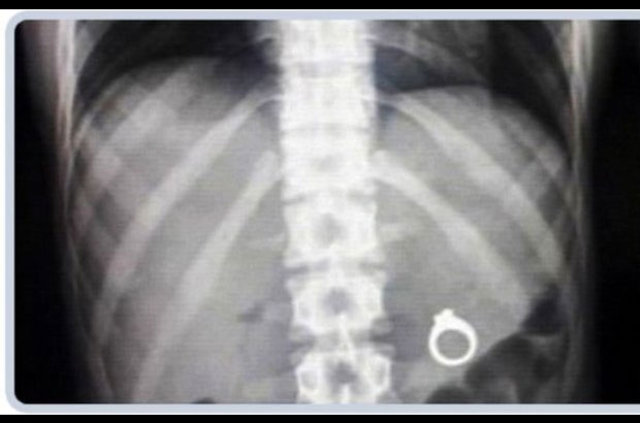

İzmir'deki Tepecik Eğitim ve Araştırma Hastanesi Çocuk Gastroenteroloji Bölümü'nün, yabancı cisim yutan çocukların nefes ve borusu ile midelerinden çıkarttığı, anahtarlık, madeni para, saat pili, ataç, çengelli iğne ve çivi gibi objeler görenleri şaşkına çevirdi.

Çocukların nefes ve borusu ile midelerinden çıkartılan, anahtarlık, madeni para, saat pili, ataç, çengelli iğne ve çivi gibi objeler görenleri şaşkına çevirdi. Anne ve babaların çok dikkatli olması gerektiğini söyleyen Doç. Dr. Maşallah Baran, şöyle dedi:

Genellikle yabancı cisimler 'X' ışınıyla görülebilir. Direk grafi ile metal ve 'X' ışınına duyarlı cisimleri rahatlıkla görebiliyoruz. Ama plastikleri göremiyoruz. Bu durumda oyuncağın bir parçasıyla yutulan parçayı anlamaya çalışıyoruz."

Bir diğer sık karşılaştığımız durum ise pil yutmaları, bunlar yakıcı olduğu için bekleme süresinde 48 saati geçirmemeye özen gösteriyoruz. Pilin vücutta bulunduğu yer de müdahale etme koşullarını değiştirebiliyor.